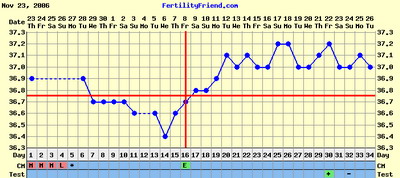

Nem tudom, hogy ez normális-e, miközben minden hormonom rendben, és a hőgörbe mutat pé-t. Meg van pozitív LH tesztem is...

Gaby: a Te görbéd elég cikkcakkos, szerintem később pé-zel...Végülis hathatott a párodnál már a gyógyszer, ha nem is drasztikusan, de már jobbak lehetnek az eredményei...